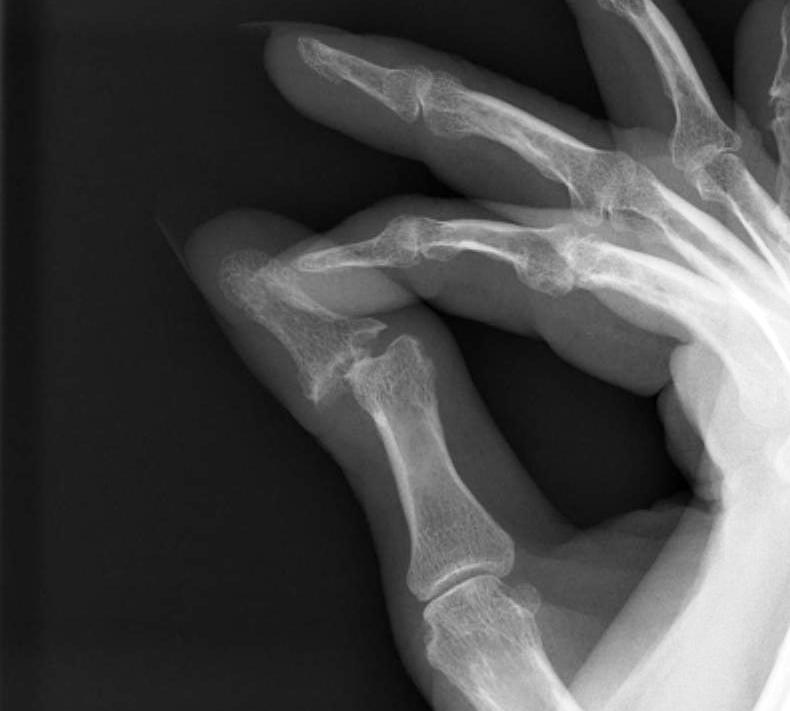

Type VI - Arthritis Mutilans

- destruction and instability MCPJ / IPJ

- arthrodesis only option